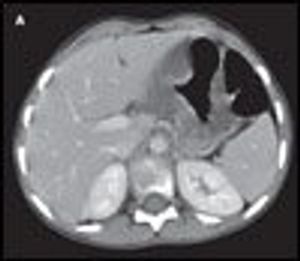

A 22-month-old boy with failure to thrive presented with a 3-day history of rhinorrhea, fever, and abdominal pain associated with tube feeding. A PEG tube had been placed 2 months before this visit.